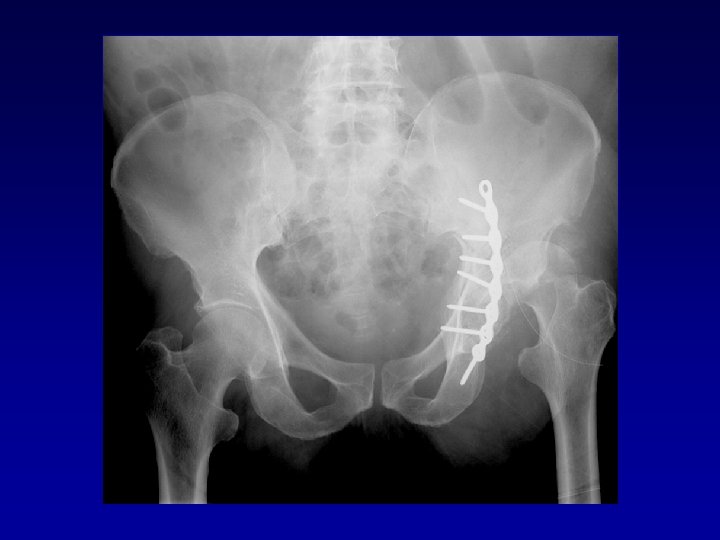

Déformation du cotyle • Ascensionné • Perte de substance osseuse scanner • Pseudarthrose •

Déformation du cotyle • Ascensionné • Perte de substance osseuse scanner • Pseudarthrose • Perte du positionnement exact (idem LCH) • Doit être reconstruit et recentré

Chirurgie préalable Le matériel en place • Gêne le creusement, la reconstruction Les complications

Chirurgie préalable Le matériel en place • Gêne le creusement, la reconstruction Les complications • Nerveuses : sciatique, crural, fessiers (EMG) • Infectieuses

Arthroplastie totale de hanche sur fracture du cotyle complexe Recentrage, reconstruction, orientation du cotyle • • Greffe Ostéosynthèse par plaque MK Surtout si pseudarthrose Réduction de la luxation